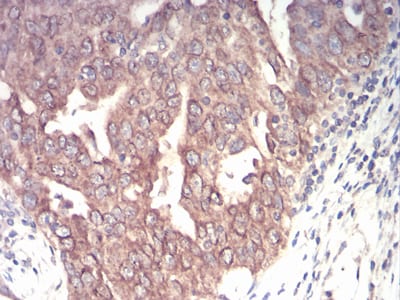

Immunohistochemical analysis of paraffin-embedded human ovarian cancer tissues using EMD mouse mAb with DAB staining.